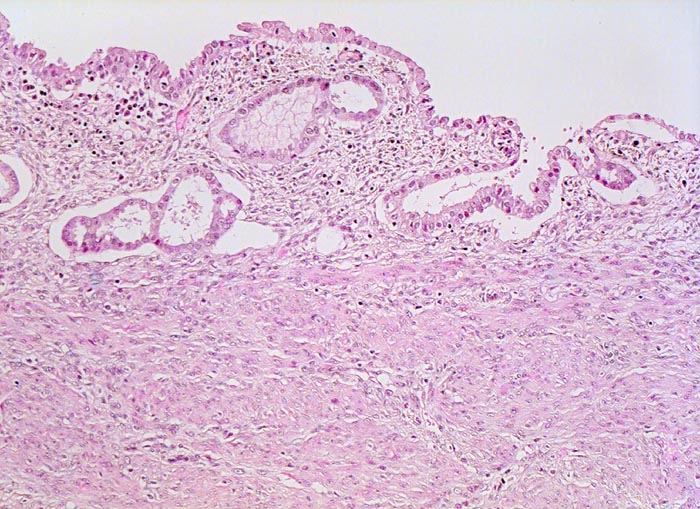

atrophes Endometrium

Hypoplasie/ Involution/ Atrophie

Uterus

Das Endometrium besteht aus vereinzelten Drüsen mit atrophem Epithel und wenig zellarmem Stroma.

Exophytischer, in das Uteruscavum hineinragender, weicher fokal hämorrhagischer Tumor ausgehend von der Uterushinterwand. Das Tumorgewebe infiltriert die innere Hälfte des Endometriums.

Postmenopausale Blutung. Diagnose eines endometrioiden Adenokarzinoms in der Corpuskurettage. Daraufhin Hysterektomie, Adnexektomie und Lymphadenektomie.

Hoch und mässig differenzierte endometrioide Karzinome sind oftmals mit einer Hyperplasie des Endometriums assoziiert, wenig differenzierte Karzinome wie im vorliegenden Fall eher mit einem atrophen Endometrium.